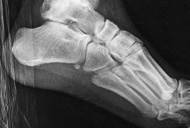

Standard orthogonal radiographs (anteroposterior and lateral) are sufficient for initial diagnosis, but they routinely underestimate the complexity of partial articular fractures. A high-resolution computed tomography (CT) scan with two-dimensional multiplanar reformats (coronal and sagittal) and three-dimensional surface rendering is considered the standard of care.

CT imaging is critical for:

1. Identifying the exact location and size of the articular fragments.

2. Detecting central articular depression that is obscured by the cortical rim on plain films.

3. Mapping fracture lines extending into the diaphysis.

4. Planning the surgical approach to ensure direct access to the primary fracture line.

Image